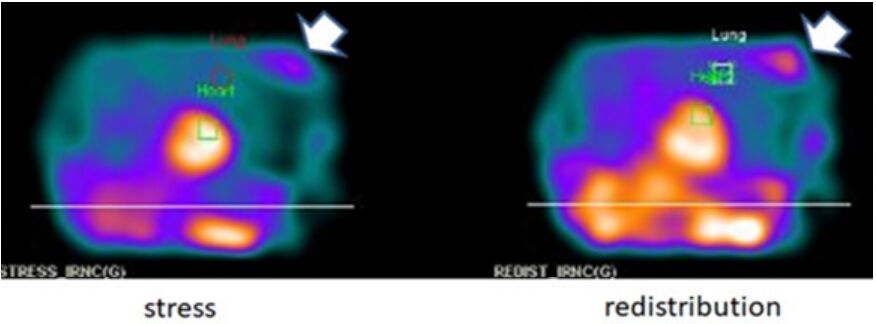

42.二歲女童反覆泌尿道感染,欲安排相關的檢查,下列敘述何者正確?(A)核醫檢查會造成較多輻射暴露,因此不應用於兒科病人 (B)超音波確認有單側水腎,可確認泌尿道感染因膀胱輸尿管逆流(vesicoureteric reflux, VUR)造成,應立刻安排手術處理 (C)可用直接放射性同位素膀胱造影檢查(direct radionuclide cystography),評估膀胱輸尿管逆流 (vesicoureteric reflux, VUR)(D) 99mTc-DTPA 檢查可評估幼兒膀胱輸尿管逆流(vesicoureteric reflux, VUR)併發的腎臟疤痕(renal scarring)